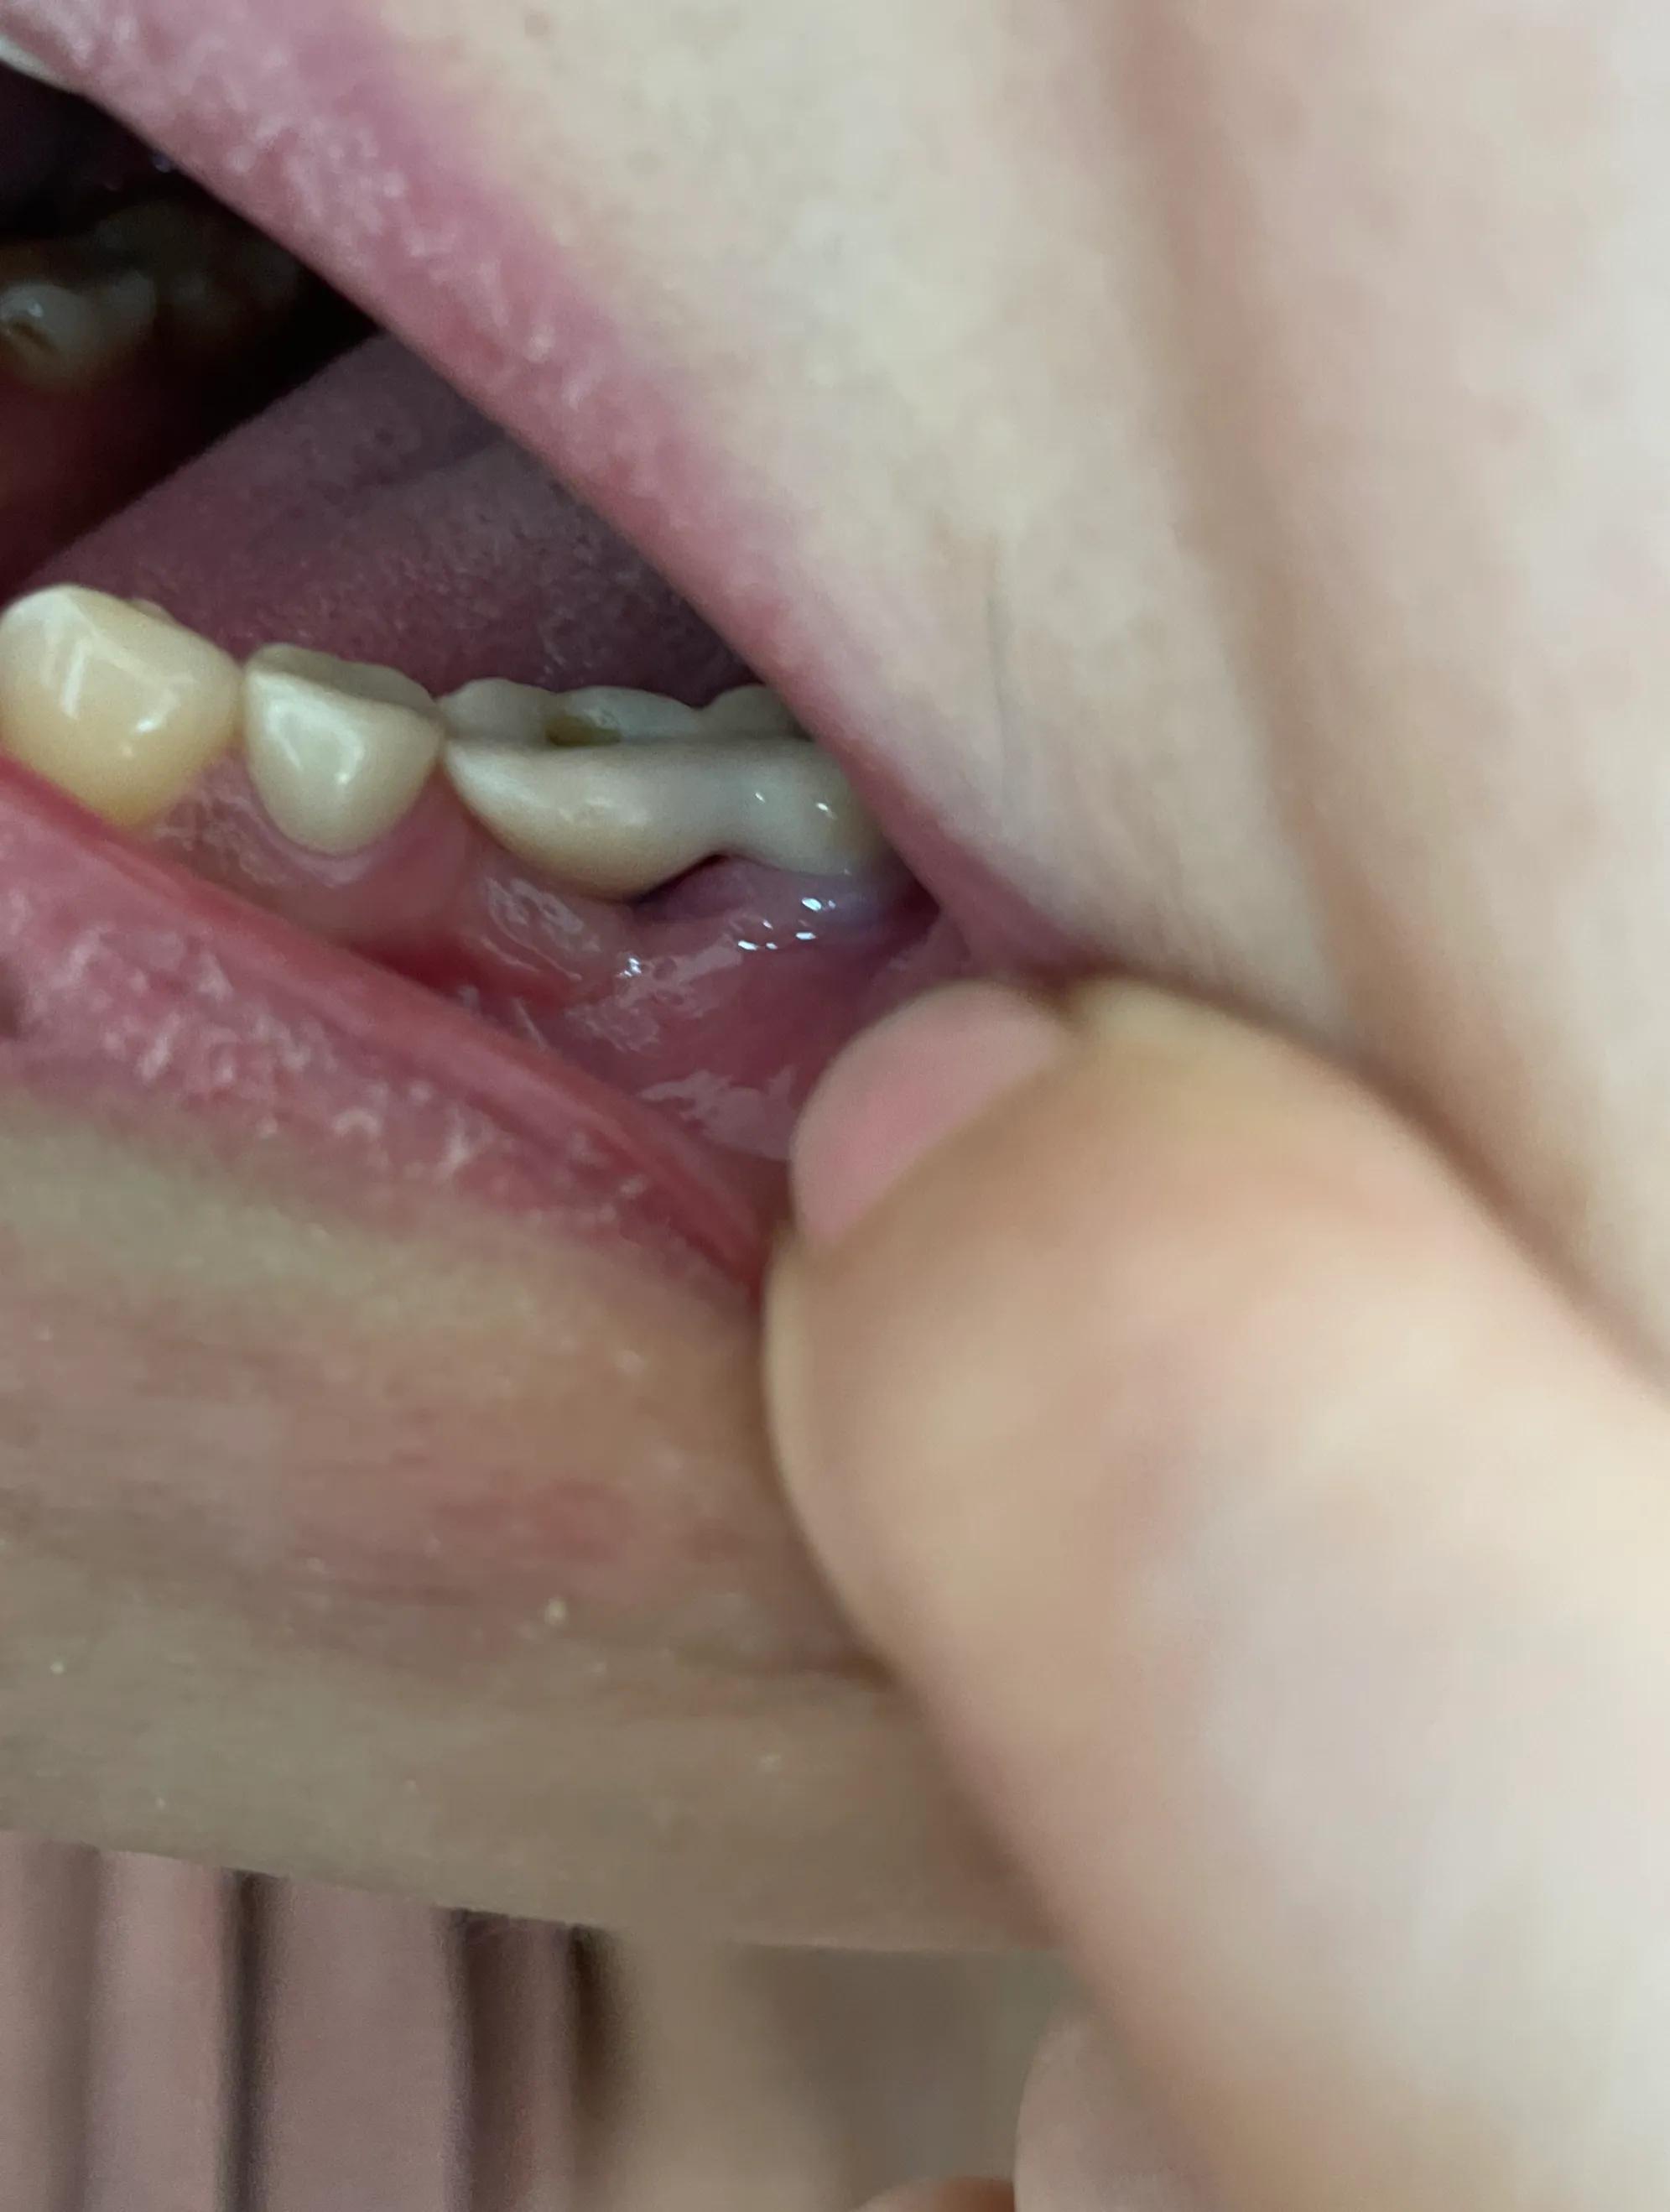

第二副牙帶好 發(fā)現(xiàn)牙齦又缺肉了 更別提貼合牙齒了 而且是一直的疼 一直難受

牙齦是外翻和牙齒分開(kāi)的 顏色發(fā)白 和其他部位牙齦不是一樣顏色

我不是專業(yè)醫(yī)生 不懂他們所說(shuō)的正常現(xiàn)象都包括什么 要怎么后期維護(hù) 我現(xiàn)在先不講看不見(jiàn)的難受 疼 先講直觀能看見(jiàn)的 他們哪位醫(yī)生可以做到把大米粒塞到牙齒下面 和將近半厘米的塑料條塞過(guò)他們的牙齒 吃過(guò)東西就要用沖牙器 不然隔頓就臭了

沒(méi)辦法自己又出去拍片子 找原因 看了幾家醫(yī)院 才知道連種植體也種偏了 牙冠也沒(méi)有就位………